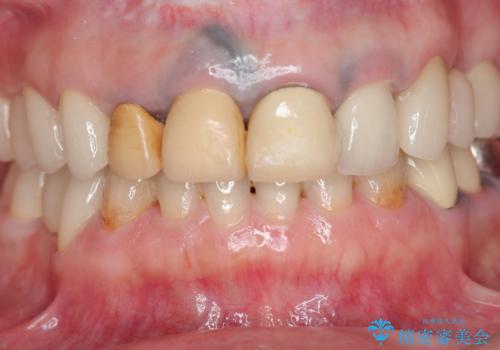

- 変色の進んでしまった前歯を審美的なセラミック治療にしたい、と希望され来院されました。

10数年前に治療を行った保険適応の硬質レジン前装冠は変色劣化が進み、審美的に問題があるだけでなく虫歯のリスクも高くなり好ましくない状況です。